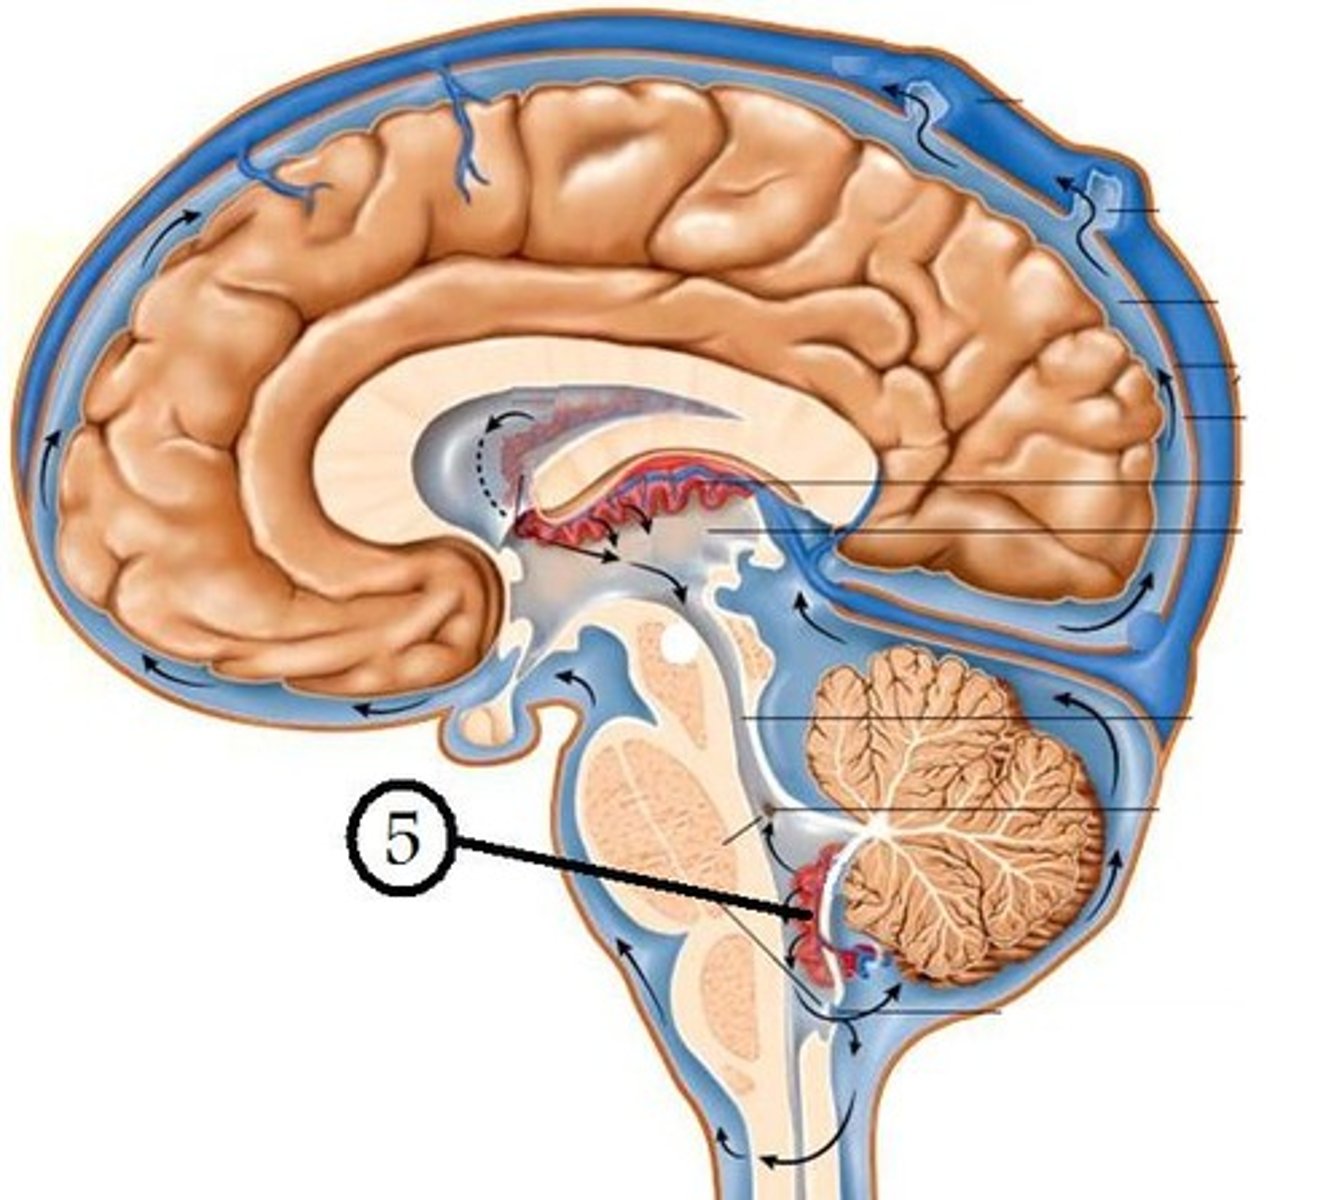

What anatomical aspect of the 4th ventricle is considered its floor?

ventral

refers to the floor of the 4th ventricle

rhomboid fossa

What forms the floor (rhomboid fossa) of the 4th ventricle?

dorsal surfaces of pons tegmentum and open medulla

inferior angle of the floor of the 4th ventricle

obex

vertical groove running in the floor of the 4th ventricle that separates it into right and left halves

dorsal median sulcus

vertical groove lateral to the dorsal median sulcus of the 4th ventricle

**same one that separated the alar and dorsal plates in the neural tube during development

sulcus limitans

refers to most of the floor of the 4th ventricle lateral to the sulcus limitans

**namesake nuclei are here

vestibular area

triangular region located in the caudal portion of the rhomboid fossa of the 4th ventricle, where the dorsal motor nucleus of CN X is

vagal trigone

Which parasympathetic nucleus is found in the vagal trigone of the 4th ventricle?

dorsal motor nucleus of X

triangular region located most medially in the caudal portion of the rhomboid fossa of the 4th ventricle, where the CN XII nucleus is

hypoglossal trigone

part of the 4th ventricle superior to the vagal and hypoglossal trigones (still medial to the sulcus limitans)

medial eminence

small bump located in the caudal portion of the medial eminence which forms from the motor fibers of CN VII as they wind around the underlying CN VI nucleus

facial colliculus

pigmented area that looks blue near the superior aspect of the sulcus limitans; cluster of noradrenergic cells

locus ceruleus

fibers that run horizontally in the central region of the rhomboid fossa of the 4th ventricle

stria medullares

area that helps to make the walls of the obex and is thought to be the "vomit trigger"

area postrema

What anatomical aspect of the 4th ventricle is considered its roof?

dorsal

What forms the superior portion of the roof of the 4th ventricle? (A)

superior cerebellar peduncles

inverted V shaped interval between the superior cerebellar peduncles that is filled by a thin layer of white matter

superior medullary velum

lower portion of the roof of the 4th ventricle formed by a thin layer of pia mater and ependymal cells

inferior medullary velum

structure attached to the ventral surface of the inferior medullary velum in the 4th ventricle that helps form CSF

choroid plexus

opening in the caudal aspect of the inferior medullary velum that allows CSF from the 4th ventricle to flow into the cisterna magna of the subarachnoid space

foramen of Magendie (or median aperture)

What mostly forms the lateral walls of the 4th ventricle?

inferior cerebellar peduncles and choroid plexus

openings in the 4th ventricle that allows CSF to flow from the 4th ventricle into the pontine cistern of the subarachnoid space

foramen of von Luschka (or lateral apertures)